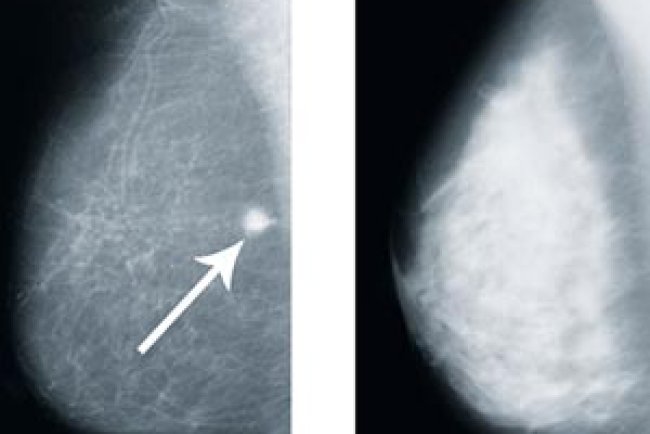

Dense Breasts on a Mammogram: What It Means and What Yo...

You’ve just opened your mammogram results. Relief sets in when you see the words “normal exam.” But then, tucked at the bottom of ...